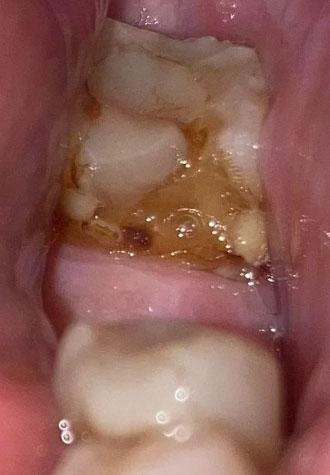

The image shows a lower back tooth (molar) with heavy brown discoloration and visible decay on the chewing surface. The tooth structure appears weakened, with plaque, food debris, and possible softening of enamel. The surrounding gum tissue looks irritated, suggesting ongoing bacterial activity.

This is a clear sign of advanced tooth decay that has been developing over time.

This case shows severe decay on a lower molar, already at high risk of nerve infection. Prompt dental treatment is critical to save the tooth and prevent abscess or extraction.